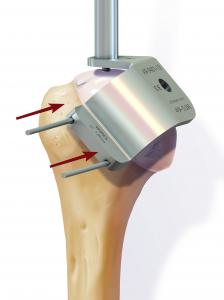

Anschließend wird der zerstörte Oberarmkopf entlang der Schnittlinie mit Hilfe einer Resektionslehre entfernt (Abb. 39). Mit einer Bohrschablone wird das Einbringen der Hohlschraube vorbereitet (Abb. 40) und die definitive Prothesengröße bestimmt. Nun kann bei freier Sicht auf die Gelenkspfanne selbige ausgetauscht werden, sofern dies aufgrund fortgeschrittener Erkrankung nötig ist (Abb. 41).

Daraufhin wird der Kalottenträger mittels der selbstschneidenden Hohlschraube im Oberarmschaft befestigt. Nun wird der endgültige Prothesenkopf angebracht (Abb. 49).